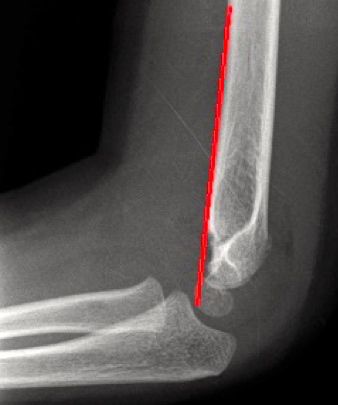

- El ángulo humeral capitelar de Baumann, estará en valgo (95% de los pacientes presentan un ángulo de Baumann con valgo 9°-26°). El ángulo de Baumann da información sobre la alineación del húmero distal y su alteración pone de manifiesto la presencia de una inadecuada reducción de una fractura supracondílea (Figura 3).